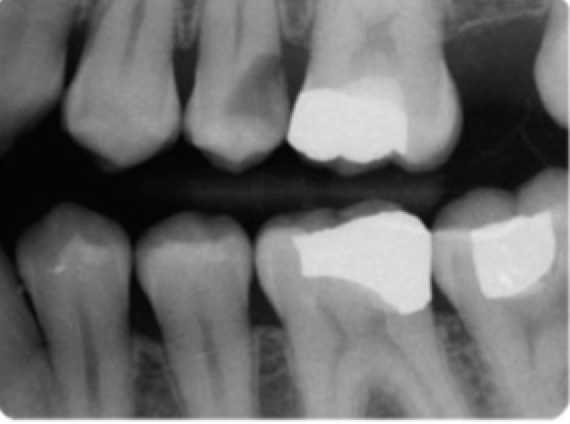

left= E Right= D1 Bottom= D2

1-E

2-D1

3-D2

4-spread of caries

1-lesion penetrates though enamel (incipient)

radiolucent triangle w/ base at enamel surface & point to DEJ

2-lesion penetrates into dentin but is less than 1/2 through thickness of dentin toward pulp

radiolucent triangular lesion in enamel and point less than halfway to dentin

3-lesion extends more than 1/2 of dentinal thickness towards pulp

4-caries spread through dentin more rapidly than enamel because dentin is softer than enamel